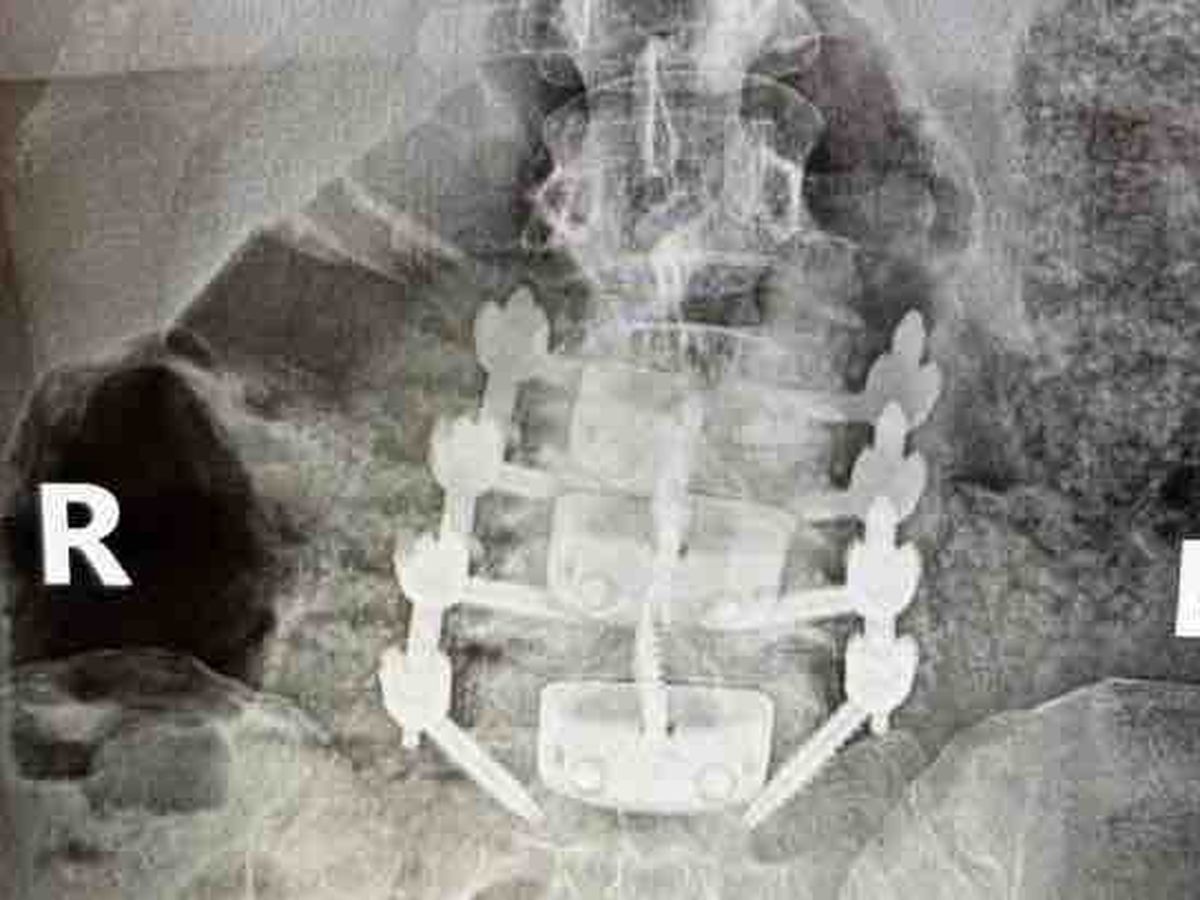

Sara was recently diagnosed with a rare congenital spine condition where her vertebrae never fully developed or connected as they should. This has led to severe scoliosis, degenerative disc disease, joint degeneration, multiple herniated discs, spondylitis, and spondylolisthesis. On top of that, doctors also discovered a tumor along her spine.

On February 26th, Sara underwent the first of multiple major surgeries—a grueling 7 hour 360-degree spinal reconstruction. Surgeons removed the tumor, inserted plastic spacers in place of damaged discs, began fusing her lumbar spine, and installed a stabilization cage to realign her vertebrae. They also took bone and bone marrow from her spine and used cadaver bone to replace it. While they believe they achieved clean margins on the tumor, she may still need chemotherapy and radiation. Once she recovers, she will face another similar surgery for her neck.